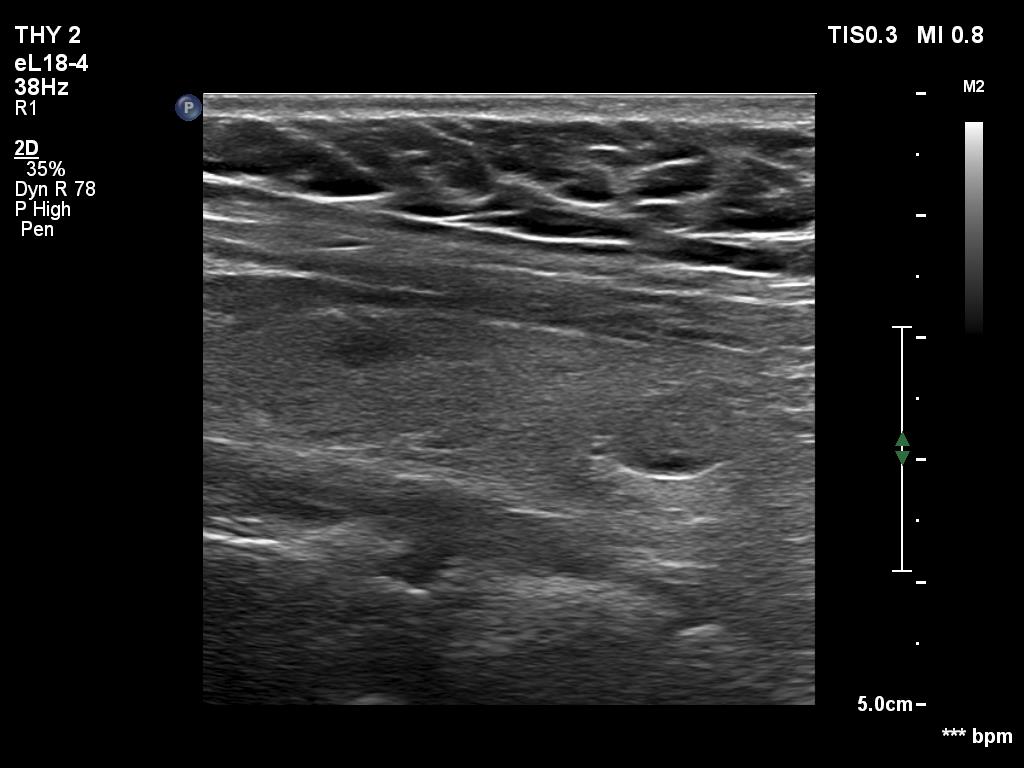

Ultrasonography. The thyroid was echonormal. Using higher frequency three discrete hypoechoic lesions were found, one in the middle dorsal part of the right lobe, one in the middle and a third one in the lower dorsal part of the left lobe. By decreasing the frequency, the presence of only the third one could be confirmed.

Comment. It is a rule that larger the distance from the probe worse the permeability of ultrasound wave. This can lead in certain patients (overweighted ones or frequently in men) that the dorsal part of the thyroid lobe can deceptively look darker, i.e. hypoechoic. If we have any doubt, by lowering the frequency i.e. increasing the penetrance, the real situation can be much better to judge.

This happened in this patient. If we would trust the pattern gained by higher frequency settings, we would falsely diagnose at least one additional nodule.